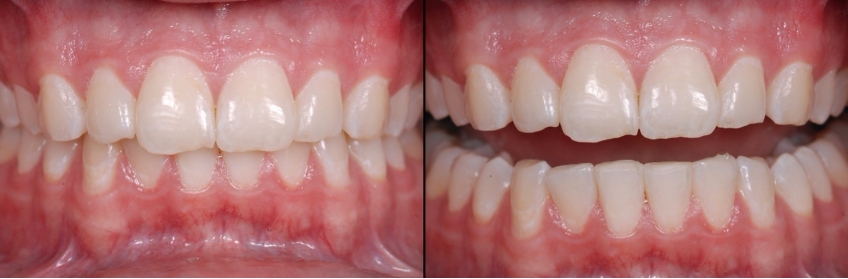

Examples of treatment options may be crown lengthening vs. intrusion to reposition overerupted anterior teeth (Figs. 6–10). You can explain each — or show the Spear Patient Education videos of each — then discuss with the patient why you believe one may be better for them.

As mentioned earlier, worn teeth typically don’t have indirect restorations, but amalgams or composites instead. This makes them easy to bond to, so you can create and try out your treatment plan with minimal to no tooth preparation and at a reasonable cost for the patient (Figs. 11–14).